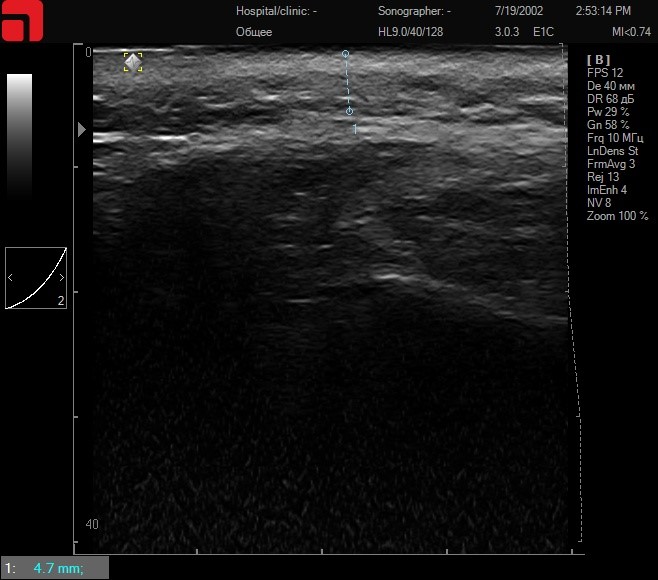

Соединительная ткань при установке каппы и сильном надавливании на манипулу

Рис. 3. Соединительная ткань при установке каппы и сильном надавливании на манипулу.

Итак, установив каппу и сильно надавливая на манипулу, манипула 4,5 мм D4 будет работать с соединительной тканью SMAS-слоя, что значительно повышает эффективность процедуры. Интенсивность надавливания на манипулу, а также использование дополнительных инструментов может напрямую влиять на глубину расположения соединительной ткани, так как работа ведется с мягкими тканями, которые можно распластать, влияя на глубину их расположения. Таким образом, при проведении ультразвукового сканирования кожи перед процедурой оценивается интенсивность надавливания на манипулу для оптимального попадания по целевым структурам.